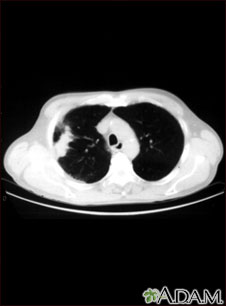

Tomografía computarizada del pulmón con cáncer de células escamosas

Pulmón con cáncer de células escamosas - Tomografía computarizada

Esta tomografía computarizada muestra un corte transversal de los pulmones de una persona con cáncer pulmonar. Las dos áreas oscuras en el centro de la pantalla son los pulmones y las áreas claras en el pulmón derecho representan el cáncer (lado izquierdo de la imagen).